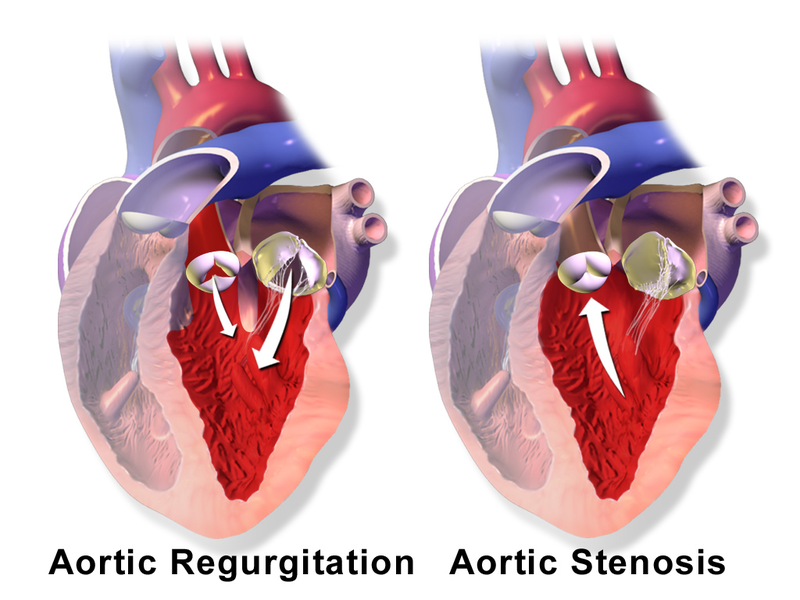

Aortic Stenosis

Aortic stenosis occurs when the aortic valve orifice narrows.

Aortic stenosis is typically brought on by fibrosis and calcification from wear and tear.

Aortic stenosis usually effects individuals above 60-years-old.

Risk factors for developing aortic stenosis include:

- Having a bicuspid aortic valve

- Rheumatic valve disease

Aortic stenosis causes a crescendo-decrescendo murmur after a systolic ejection click.

Complications of aortic stenosis include:

- Concentric left ventricular hypertrophy

- Angina

- Syncope

- Cardiac failure

- Microangiopathic hemolytic anemia

Treatment of aortic stenosis is valve replacement.

Aortic Regurgitation

Aortic regurgitation is the backflow of blood from the aorta into the left ventricle during diastole caused by aortic root dilatation or valve damage.

Aortic regurgitation is the most common cause of isolated aortic root dilation.

Clinical features of aortic regurgitation include an early, blowing diastolic murmur and hyperdynamic circulation due to increased pulse pressure.

Aortic regurgitation results in left ventricle dilation and eccentric hypertrophy due to volume overload.

Treatment of aortic regurgitation is valve replacement once left ventricle dysfunction develops.